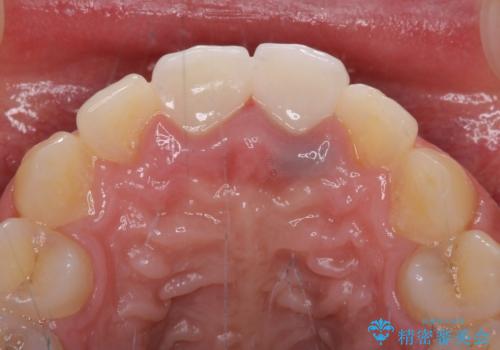

下顎前歯の部分矯正に半年ほどかかってしまい、少し期間は長いものとなりましたが、上下ともに前歯がきれいに整い、患者様には大変満足していただきました。